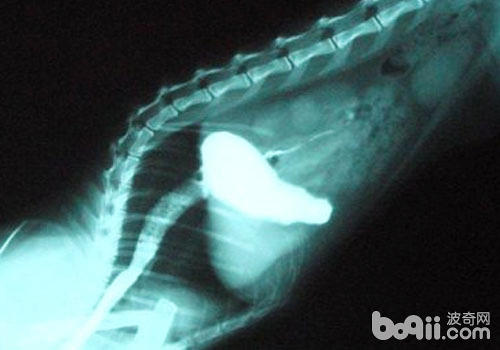

如果我們判斷貓咪是之前吞食了腐蝕性物質(zhì)而引起食道瘢痕組織的形成,導(dǎo)致食道狹窄,我們用食管鋇餐造影X線檢查,可顯示狹窄病變的部位、程度和范圍。因化學(xué)品灼傷造成的食管狹窄常呈現(xiàn)食管腔狹小,狹窄段長(zhǎng),邊緣不規(guī)則,粗細(xì)不均勻,食管壁僵硬,鋇劑呈粗細(xì)不等的影像進(jìn)入胃部,或食管腔高度梗阻,鋇劑不能通過。食管炎引致的狹窄常位于食管下段,病變范圍比較局限。病程長(zhǎng)、狹窄程度重的病例,上段食管可能擴(kuò)大。手術(shù)后食管狹窄,則食管腔常呈局限的環(huán)狀狹窄。

食道狹窄造影